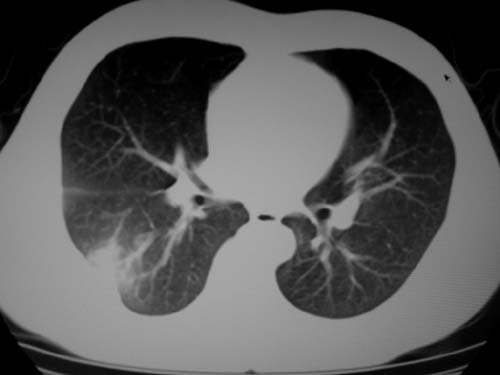

标题: CT19540: 31岁。自述结核性胸水治疗两个月后,在外院拍x线发 [打印本页]

标题: CT19540: 31岁。自述结核性胸水治疗两个月后,在外院拍x线发

右侧胸壁结节状软组织影伴相应肺叶内受侵,伴右侧胸腔积液。考虑:结核性可能大。

病灶也是发生于结核球好发部位,支持结核

考虑结核性结节

右侧胸壁结节状软组织影伴相应肺叶内受侵,伴右侧胸腔积液,结合临床,首先考虑结核。

考虑结核性胸膜炎,胸膜肥厚,不除外胸膜间皮瘤可能,建议复查。

1)考虑右侧结核性胸膜结节。2)右侧胸膜增厚+包裹性胸腔积液。